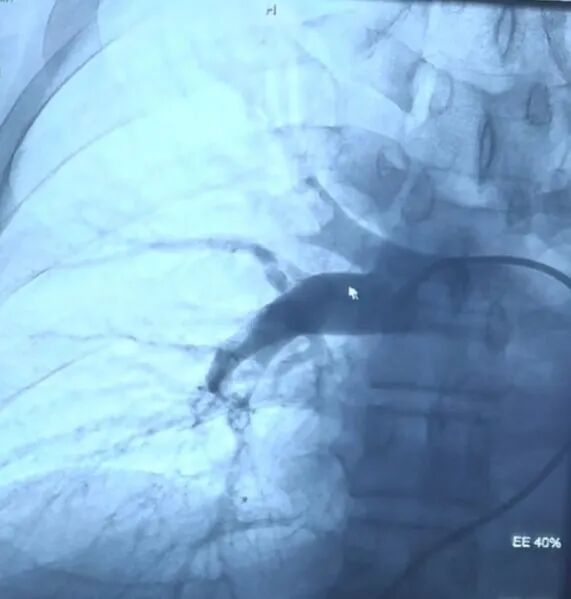

更换加硬导丝,更换戈尔DSF1633短鞘,导丝、Pigtail导管、指引导管配合,导管置于肺动脉行造影示左肺动脉主干显影可,左上肺动脉显影可,左下肺动脉充盈缺损,更换加硬导丝,腾复肺动脉取栓系统抽吸血栓,再次造影示左下肺动脉显影好转。导管置于肺动脉行造影示右肺动脉主干显影可,右肺叶中动脉、上动脉可见充盈缺损,右肺下动脉显影可,更换加硬导丝,腾复肺动脉取栓系统抽吸出暗红色血栓,取出血栓送病理检查,再次造影示右肺叶中动脉、上动脉显影好转。

术前造影

术后造影

患者术中情况平稳,症状得到改善,肺动脉压由术前44mmHg降低为术后31mmHg,血氧饱和度由90%上升至97%,氧分压由术前60.5mmHg上升至78mmHg,迅速转危为安。